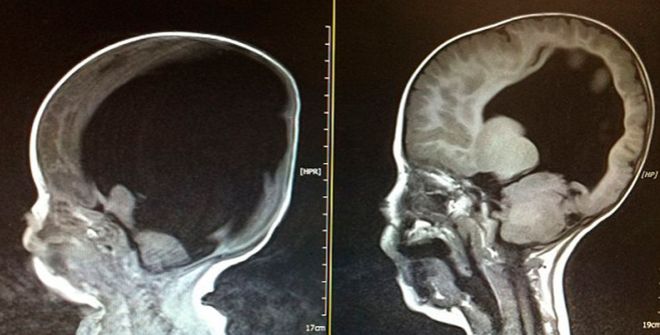

La cabeza de Noah. Los dos escáneres que muestran cómo el niño británico nació sin apenas masa encefálica. Hoy tiene cuatro años y ha pasado de un 2% de función cerebral a un 70%.

A los padres les dijeron que se prepararan para lo peor. El niño que esperaban, si sobrevivía al parto, tendría un futuro horrible, se quedaría discapacitado mental y físicamente. La espina bífida y la hidrocefalia le habían dejado sólo un 2% de función cerebral. Y Shelly, que estaba de 12 semanas, se derrumbó. «Empecé a preparar su entierro mientras estaba embarazada», admitió la madre, de 44 años, en el medio digital inglés Cumberland News & Star. Las pruebas mostraban que en la cabeza de Noah (foto izquierda) había más líquido que masa gris, un cerebro poco mayor que una naranja. Una rara anomalía que ponía fecha de caducidad a la existencia del pequeño Noah: 15 días de vida tras el alumbramiento. Y, sin embargo, a los dos años, estaba sentado derecho, cantando, e incluso jugando con la PlayStation. Y progresando.